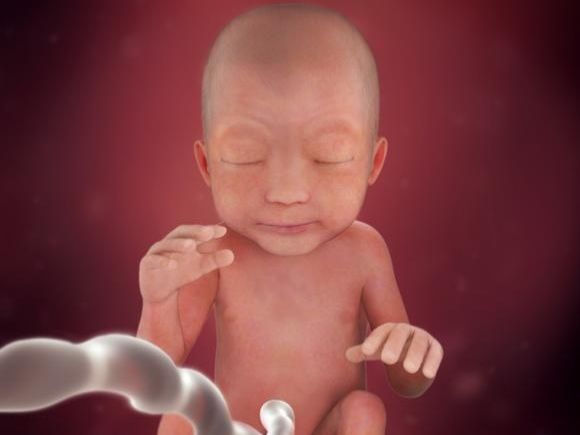

Placenta a její vliv na plod

Plodové lůžko neboli placenta poskytuje děťátku v děloze vše potřebné .

Zásobuje především miminko živinami a kyslíkem. Placenta...

13. týden těhotenství

Maminka

Tento týden je poslední z prvního trimestru. Rizikovost potratu se minimalizovala. V následujících týdnech byste si měla...

12. týden těhotenství

Maminka

Těhotenské oblečení začíná být vašim nejlepším společníkem, vaše děloha se podstatně zvětšila. Vás gynekolog je schopen...

11. týden těhotenství

Maminka

Vaše nevolnost postupně ustupuje a díky tomu máte i víc energie. Nyní však můžete začít trpět na zácpu, ta je způsobená...